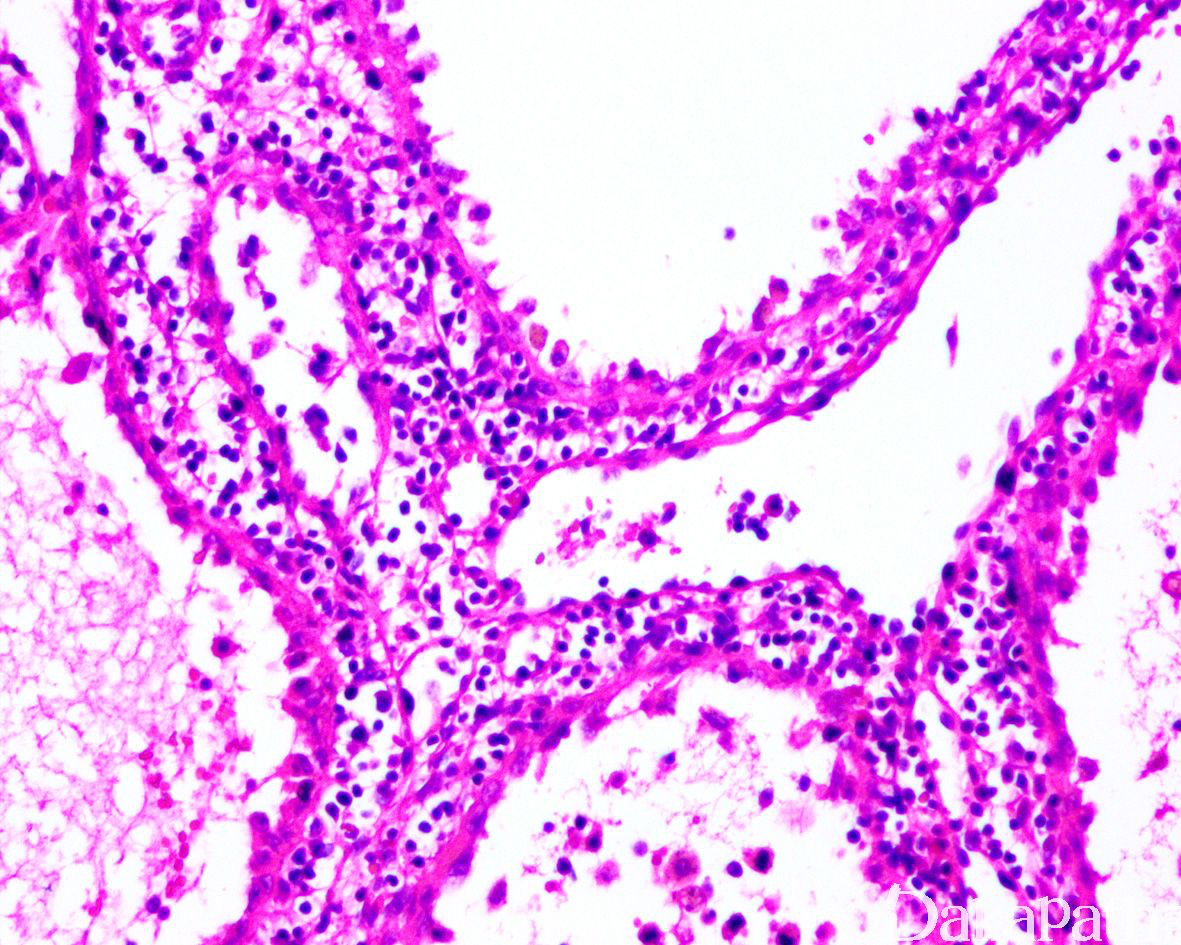

- 结节大小不一,由形态一致的血管互相吻合成网状,似脾窦;

- 血管腔不规则,部分囊状扩张伴突向血管腔的具纤维性间质轴心的乳头结构,其表面衬覆单层内皮细胞;

- 内皮扁平或高柱状,常脱落至血管腔内,常见吞噬红细胞现象或含铁血黄素,可呈泡沫样;

- 部分内皮细胞胞质内充满 0.5 ~ 2μm 大小的嗜伊红色小球的窦岸细胞,为该血管瘤的特征性细胞,电镜下,这些小球由溶酶体和线粒体聚集形成;

- 内皮细胞一般无异型,核分裂很少或无,少数病例中,瘤细胞可出现明显的异型性.核分裂活跃,可称为窦岸细胞血管肉瘤